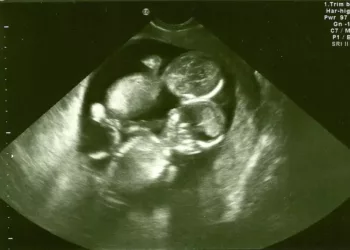

Kate Lucas și soțul ei aveau doi copii, dar au decis că vor să mai aducă un copilaș pe această...